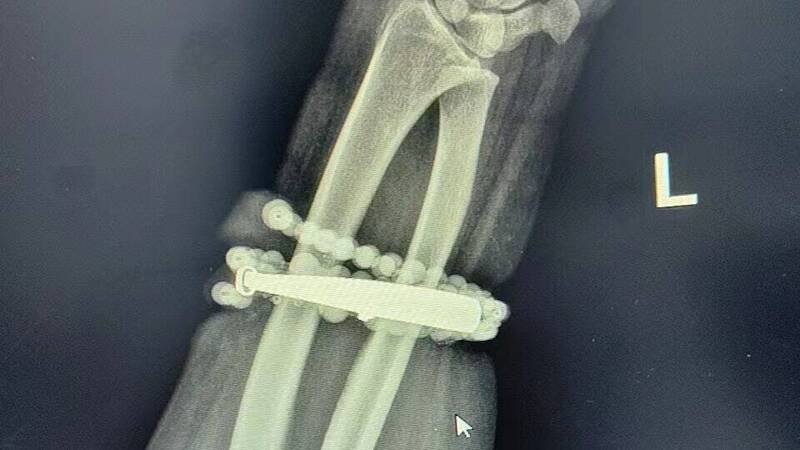

由于感染严重,医疗团队决定采取手术处理。主刀医师形容,手术过程如同「考古挖掘」,必须沿著手镯与串珠的形状,小心翼翼地将被肉芽组织「吞噬」的部分分离出来,避免伤及血管与神经。历经约1小时的精细操作,手术团队才成功取出已失去光泽的首饰。术后龚女感激地表示:「真的太谢谢医生了,我以为我的手保不住了!」

手镯和串珠链「长」进肉里。(图:福建卫生报)

中国福建一名33岁龚姓女子戴银手环和串珠长达10年未摘下,竟长进肉里,差点要截肢。(图翻摄自微博)